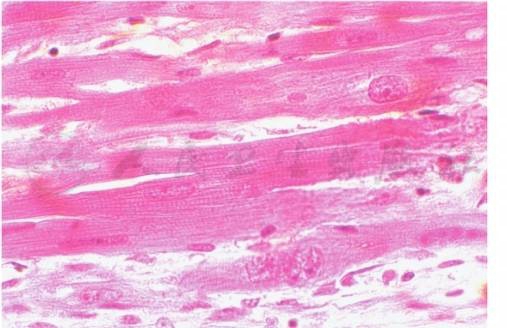

2.黄绿青霉素对大鼠心肌损伤的形态和生化毒理

饲喂15mg/kg CIT可使大鼠心肌发生变性和坏死,呈灶状或条索状分布,涉及面较大,有多量淋巴细胞和单核细胞浸润,肌原纤维凝集崩解,部分心肌细胞颗粒或空泡变性。电镜下实验组心肌细胞核固缩,肌丝溶解,结构明显紊乱,Z线(Z-band)增粗,线粒体数量明显减少。CIT可使大鼠血清中乳酸脱氢酶(lactate dehydrogenase,LDH)、谷草转氨酶(glutamic oxaloacetic transaminase,GOT)、肌酸激酶(creatine kinase,CK)、肌酸激酶同工酶(creatine kinase isoenzymes,CKMB)及肌钙蛋白T(troponin T,TnT)含量增多,均存在统计学意义。